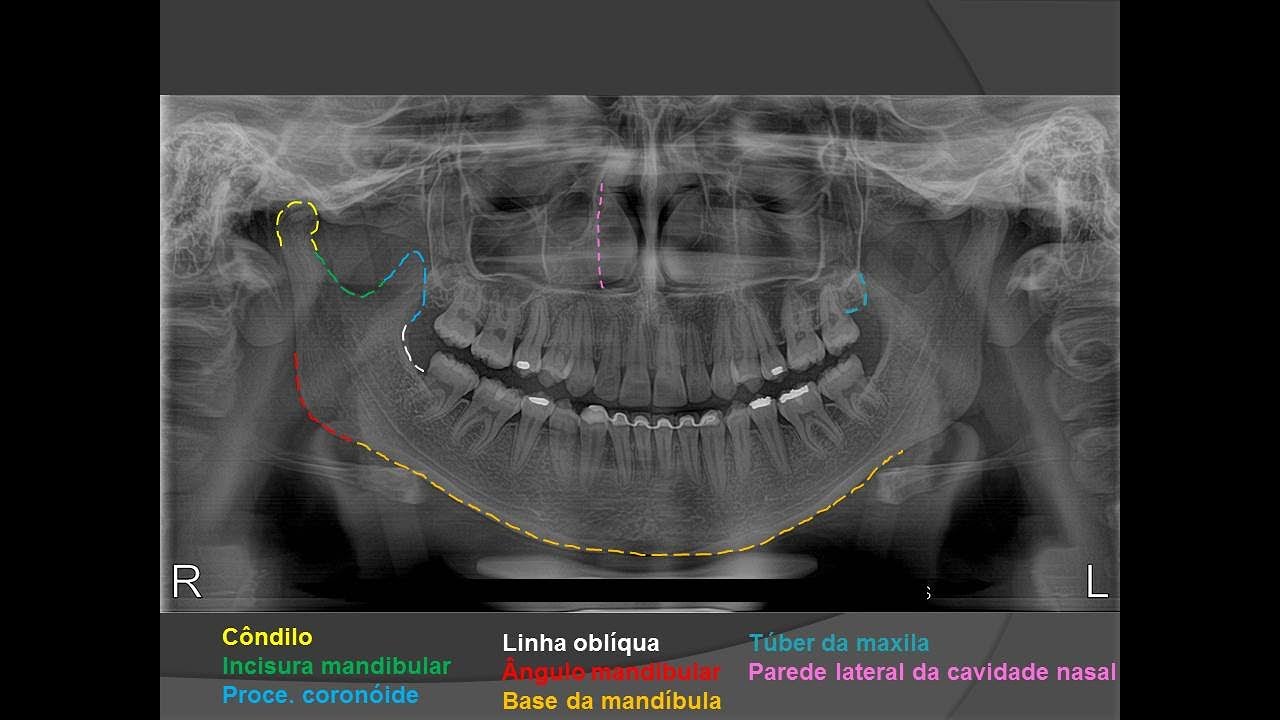

cronológica com a idade lá que está registrada no registro do paciente na no rg que tá vindo lá no exame para vocês na sala 25 anos e 5 meses é compatível com a imagem que você tem a vale a traçar o contorno de todas as estruturas anatômicas então observe se você tem uma panorâmica olha o côndilo contorna assim visualmente tá gente no daqui sótão uma marcação colocar essa imagem só para ilustrar um pouco dessa ideia mas visualmente olha lá o côndilo tá certinho olha aqui ramo de mandíbula e a região do ângulo a base outro

lado ok seio maxilar ao assoalho do seio parede anterior posterior tá tudo certinho tá tudo ok então observe a imagem e contorna essas estruturas visualmente como um todo para você observar se está tudo dentro da normalidade a observar o número de dentes presente então quantos dentes aquele paciente tem você tem que avaliar isso você tem que a identificar essas estruturas então aqui olha tem um paciente com perdas dentárias ele tem um ausência de dentes da região posterior e aí eu consigo calcular aqui olha só contar rapidinho quais são os dentes presentes aqui já uma outra